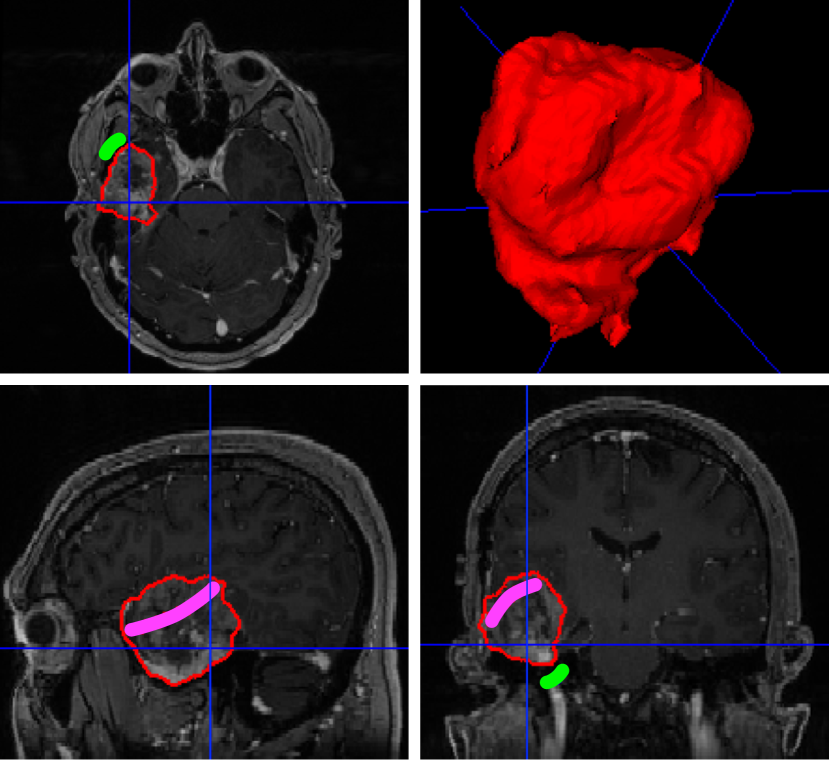

Refer to caption

Figure 1: Interactive algorithms are required to deliver context-aware artificial intelligence. In this example, using the algorithm presented in [8], brain tumour segmentation is initially performed automatically using a pre-trained algorithm. As part of the surgical planning, the user may want to refine the segmentation by providing scribbles to denote areas that should be excluded (green) or included (pink) irrespective of the initial segmentation. The algorithm then adapts its output to respect the user input.

What distinguishes segmentation in surgical planning from segmentation in diagnostic imaging is nonetheless that the objective is not necessarily always that of reaching the best performance in getting the structures delineated with sub-voxel accuracy. Surgical planning needs to respect patient-specific needs and preferences of the surgeon. This requires putting the clinical team at the centre and promoting flexible tools that integrate into the surgical workflow. Interactive deep learning methodologies are emerging to combine rich prior knowledge embedded in retrospective data from previous patients with as-sparse-as-possible annotations provided by clinicians [18, 8]. As illustrated in Figure 1, deep interactive segmentation allows the clinical expert to refine the results from an initial automated step and most importantly to adapt the inferred results on the fly based on contextual information. Furthermore, given the heterogeneity and evolving nature of surgical practice, additional flexibility is required to handle potentially missing input modalities. Recent work in deep machine learning are focusing on dealing with such dynamic hetero-modal context while exploiting heterogeneous sources of data for the training process [19, 20]. Bringing flexible machine learning tools to maturity will certainly play an important role in supporting the clinical adaption of AI in surgery.